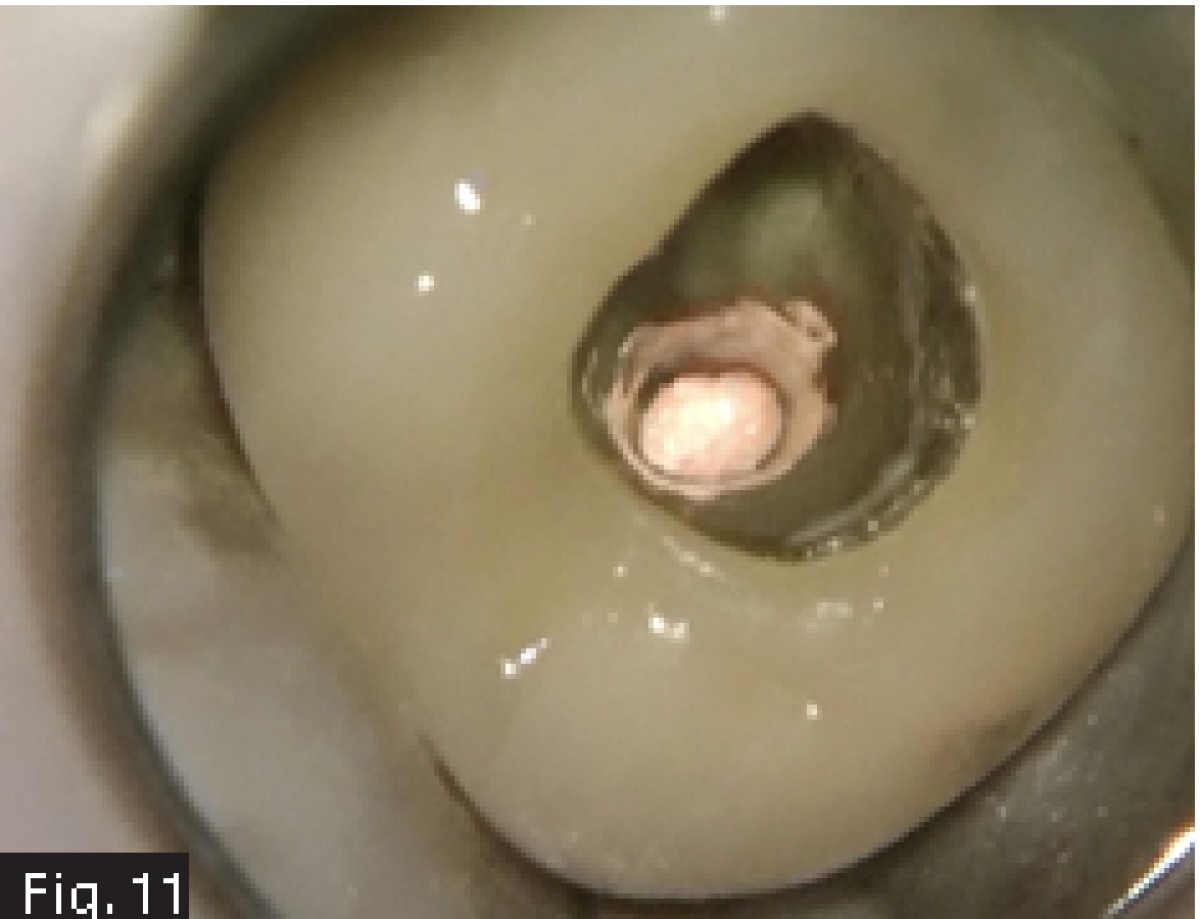

A 62 years old patient was referred to our clinic for endodontic retreatment: the patient reported swelling to the upper left part of the gum. The radiographic examination showed the presence of an existing endodontic therapy and of periapical radiolucencies (Fig. 1). Since the existing therapy could be improved, we decided to retreat the tooth passing through the existing crown. After positioning the rubber dam (Fig. 2), the existing composite filling in the centre of the crown was removed by using a diamond-coated bur driven by a high-speed handpiece. In this way, the access cavity was executed and refined in order to see the pulp chamber(Fig. 3). The existing root canal filling was removed thanks to the use of rotary instruments specifically designed for retreatment, then ultrasonic tips were used to remove the remnants of the pull chamber floor. The chamber was filled with 5 % sodium hypochlorite (Fig. 4) and the MB2 canal, that had not been shaped-cleaned-filled during the initial treatment, was found and it underwent the standard protocol for shaping.

Considering the presence of an endodontic lesion and swelling, a lot of time was dedicated to decontamination of the root canal system (Fig. 5) (18). The device chosen to deliver the irrigating solution right to the working length was IrriFlex (Produits Dentaires SA, Switzerland) (Fig. 6) because, thanks to its flexibility, it was able to deliver the irrigant to the apical third of each root, without any effort, without stopping in case of curvatures. The irrigant was then activated by means of ultrasonic inserts (19) according to the indications given by Tonini et al. (12). After ensuring that the root canals were dry, they were filled according to the warm gutta percha compaction technique (Fig. 8-10). After that, the access cavity was filled by means of a direct composite restoration (Fig. 11) and a post operative x-ray was taken in order to check the final result (Fig. 12).